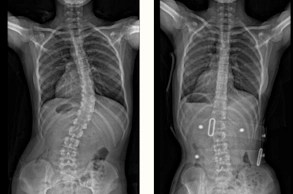

Braced for Scoliosis offers effective solutions from the original and only authentic provider of Gensingen Braces in the UK, Sally Hews of Braced for Scoliosis. The Gensingen brace by Dr Weiss works in conjunction with Schroth therapy and is primarily for adolescent and early onset (juvenile) Idiopathic Scoliosis.

Designed for maximum comfort and effectiveness, the Gensingen Brace™ is supported by years of research and clinical success. The original Gensingen Brace utilises the latest technology to provide optimum comfort and results in the treatment of Scoliosis, working alongside Schroth therapy.